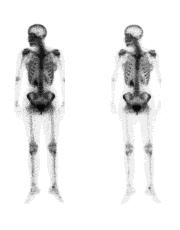

A DEXA scan is a low-radiation x-ray that measures the density of the minerals in your bones. Usually, it measures density in the spine and hip bones. Your health care provider uses this test to:

· Diagnose bone loss and osteoporosis

· Predict your risk of future bone fractures

· See how well osteoporosis medicine is working

A simple spine or hip x-ray may show fracture or collapse of the spinal bones. However, simple x-rays of other bones are not very accurate in predicting whether you are likely to have osteoporosis. A new low-radiation spine x-ray called a vertebral fracture assessment (VFA) is now often done with a DEXA to better identify fractures that do not have any symptoms.

DEXA scan results compare your bone mineral density with both a young adult who has no bone loss and with people your age and gender. This means that at age 80, almost one third of women with normal age-related bone loss would have osteoporosis, based on their DEXA scan results.